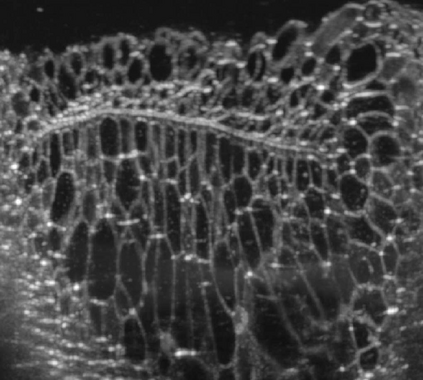

The statistical supervised learning framework assumes an input-output set with a joint probability distribution that is reliably represented by the training dataset. The learner is then required to output a prediction rule learned from the training dataset's input-output pairs. In this work, we provide meaningful insights into the asymptotic equipartition property (AEP) \citep{Shannon:1948} in the context of machine learning, and illuminate some of its potential ramifications for few-shot learning. We provide theoretical guarantees for reliable learning under the information-theoretic AEP, and for the generalization error with respect to the sample size. We then focus on a highly efficient recurrent neural net (RNN) framework and propose a reduced-entropy algorithm for few-shot learning. We also propose a mathematical intuition for the RNN as an approximation of a sparse coding solver. We verify the applicability, robustness, and computational efficiency of the proposed approach with image deblurring and optical coherence tomography (OCT) speckle suppression. Our experimental results demonstrate significant potential for improving learning models' sample efficiency, generalization, and time complexity, that can therefore be leveraged for practical real-time applications.